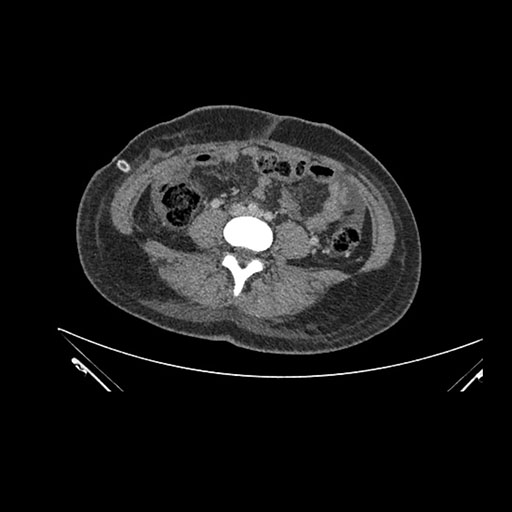

Imaging Analysis

Look through the patient's CT scan to identify any areas of concern for the necessary procedure.

Axial Venous

Based on initial findings, which issue(s) would you be most concerned about?